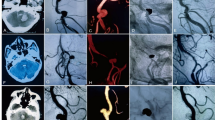

The baseline characteristics of the patients and aneurysms are shown in Table 1. A total of 28 patients (7 males and 21 females) at a mean age of 62 ± 11 years (range, 36–81 years) were included. Of the 31 aneurysms whose mean size was 21.8 ± 5.7 mm (range, 13–33 mm), 24 (77.4%) were splenic artery aneurysms (SAAs), 2 (6.5%) were superior mesenteric artery aneurysms (SMAAs), and 5 (16.1%) were renal artery aneurysms (RAAs). Besides, 25 patients (89.3%) had a single aneurysm, while three patients (10.7%) had multiple VAAs. Two patients developed two tandem SAAs, and one patient developed an SAA and an SMAA. All VAAs were saccular aneurysms in terms of morphology. Of the 26 tortuous visceral arteries, 23 (88.5%) were categorized as severely tortuous, 1 (3.8%) as moderately tortuous, and 2 (7.7%) as mildly tortuous (Fig. 1). Three patients were admitted due to pain, with two having mild abdominal pain and one having sudden right lumbar pain.